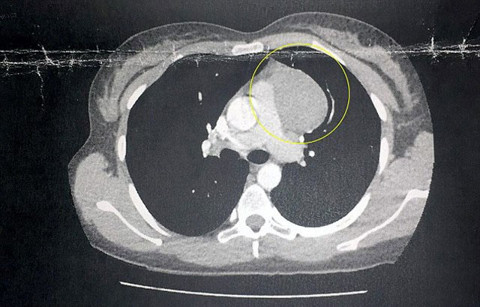

Epilasyondan tahriş oldu sandı kanser çıktı!

Genç kadın hastalığını şu sözlerle anlattı: "Daha önce böyle bir şey ne duydum, ne gördüm. Kanser olabileceği aklımın ucundan geçmezdi...